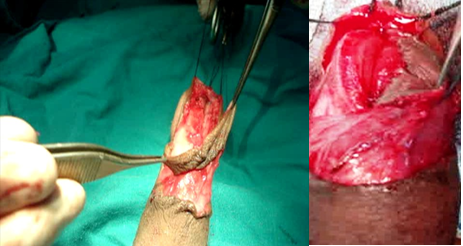

The last 3 patients with fossa navicularis stricture were proved by a biopsy to have LS. We had arranged to repair them in two stages. In the first stage, we excised the urethra completely till the healthy proximal segment with complete exposure of the glans and preparation of a well-vascularized bed as in Figure S5. Buccal mucosa was harvested from the lower lip according to the defect and a segment not more than 4cm in length and width of 1cm was folded to cover the entire defect. The graft was sutured with 6-0 Vicryl suture laterally to the skin edges on both sides till the tip of the meatus and proximally to the urethral meatus. The graft was meshed to prevent serous collection under the graft, and we had taken a tacking suture to fix the graft to the underlying tunica albuginea. A suitable silicone urethral catheter was inserted. The graft was fixed with gauze to prevent mobility. 2nd stage was after 6 months. U-shaped incision from the tip of the glans distally to around the urethral meatus proximally was carried. Lateral dissection was carried out subdermally with preservation of dartous pedicle and tubularization of the taken buccal graft with augmentation of the suture line with a second layer of dartous fascia using 6-0 Vicryl suture on a suitable silicone urethral catheter.

Figure S5 Urethrectomy for a patient with BXO.